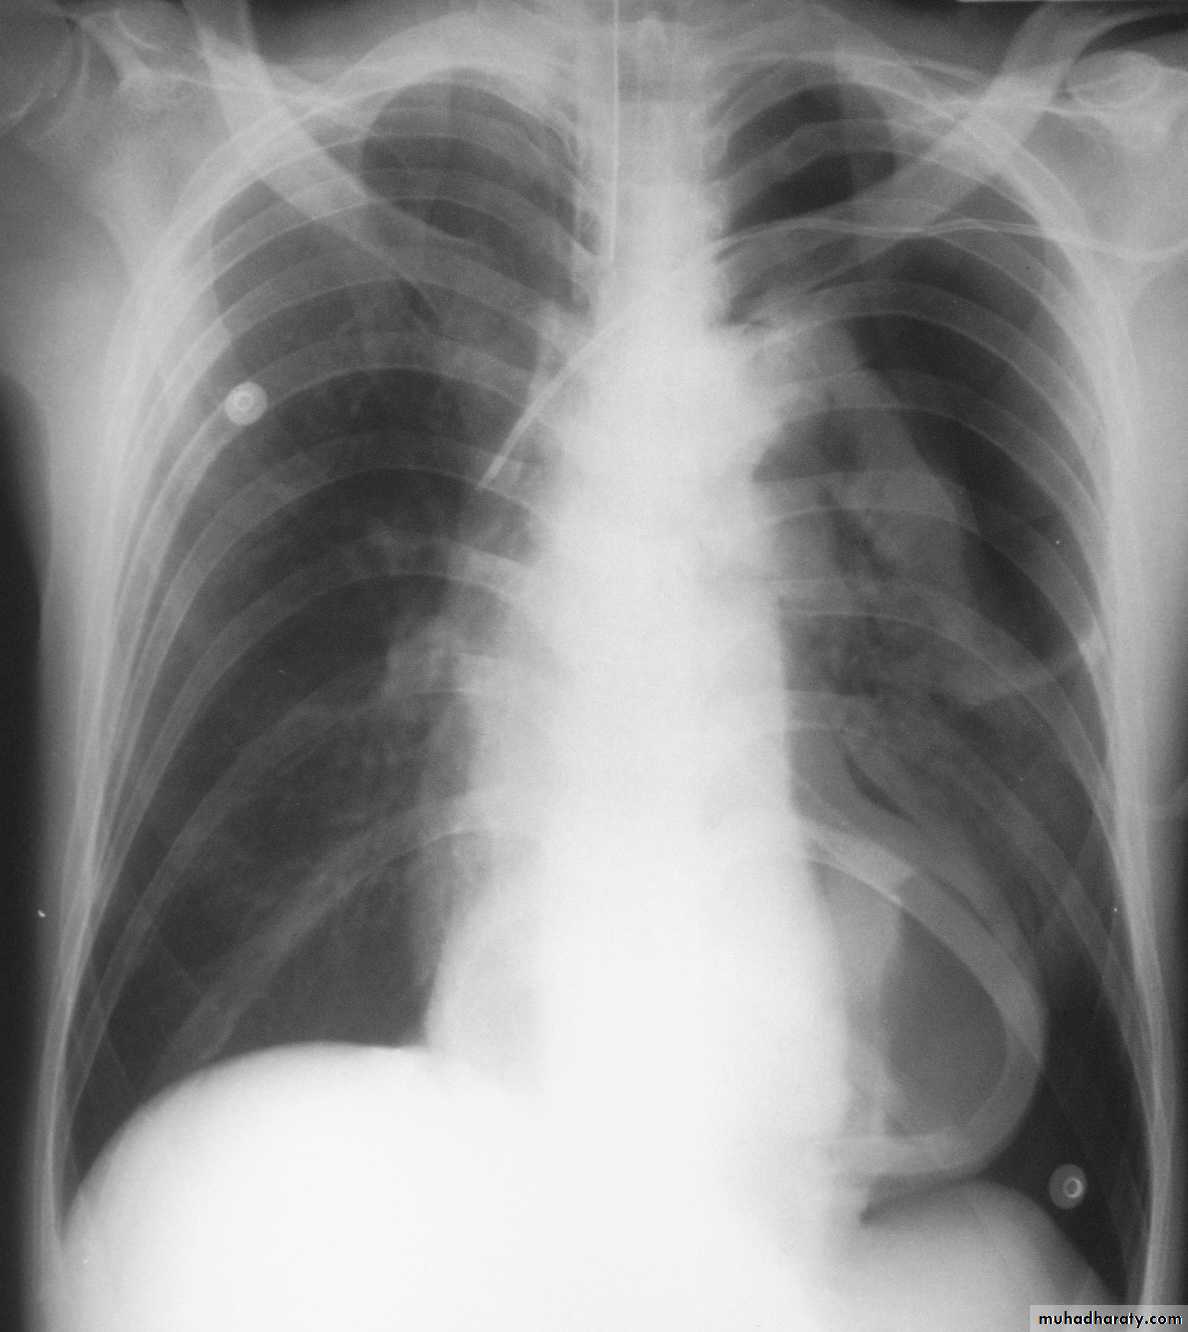

Chest X-ray: widening of the mediastinum, aspiration pneumonia.A barium swallow: tapered narrowing of the lower esophagus, esophageal body is dilated, aperistaltic and food-filled.

A 56 old woman present with four days history of breathlessness , cough and high fever. She give long history of indigestion and intermittent dysphagia to solids and liquids. On several occasions undigested food would be regurgitated back shortly after she had eaten. She would often wake at night with episodes of coughing and spluttering. There was no history of weight loss.

What type of complication the patient develop?

Nocturnal pulmonary aspiration develops.